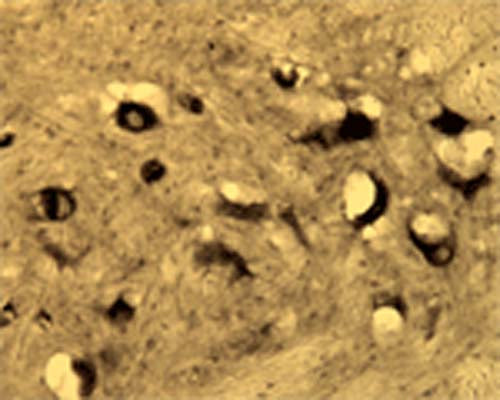

Anti-Activity-regulated gene 3.1 protein homolog (Arg3.1) Antibody

Our Anti-Activity-regulated gene 3.1 protein homolog (Arg3.1) rabbit polyclonal primary antibody detects human, mouse, and rat Activity-regulated gene 3.1 protein homolog (Arg3.1), and is IgG. It is validated for use in IHC-Frozen.